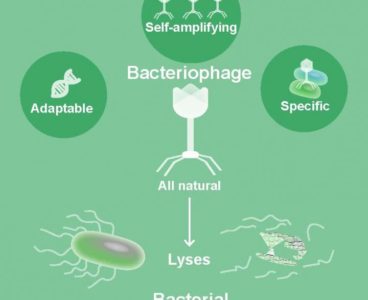

Bacteriophages, Natural Drugs to Combat Superbugs

Viruses that specifically kill bacteria, called bacteriophages, might one day help solve the growing problem of bacterial infections that are resistant to antibiotic treatment. Researchers at Baylor College of Medicine and the Michael E. DeBakey Veterans Affairs Medical Center have determined that phages can effectively reduce bacterial levels and improve the health of mice that…